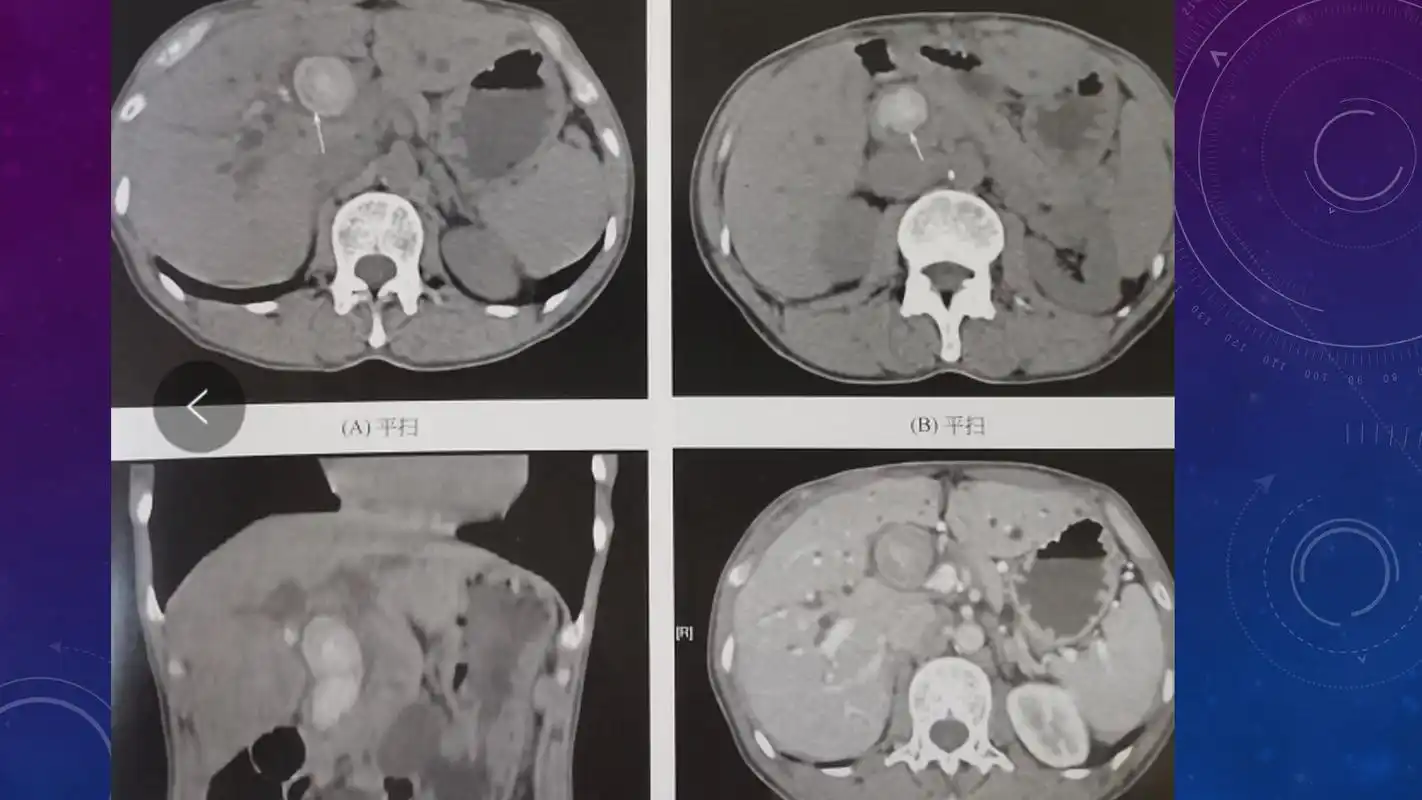

急腹症影像:胆道结石ct表现!